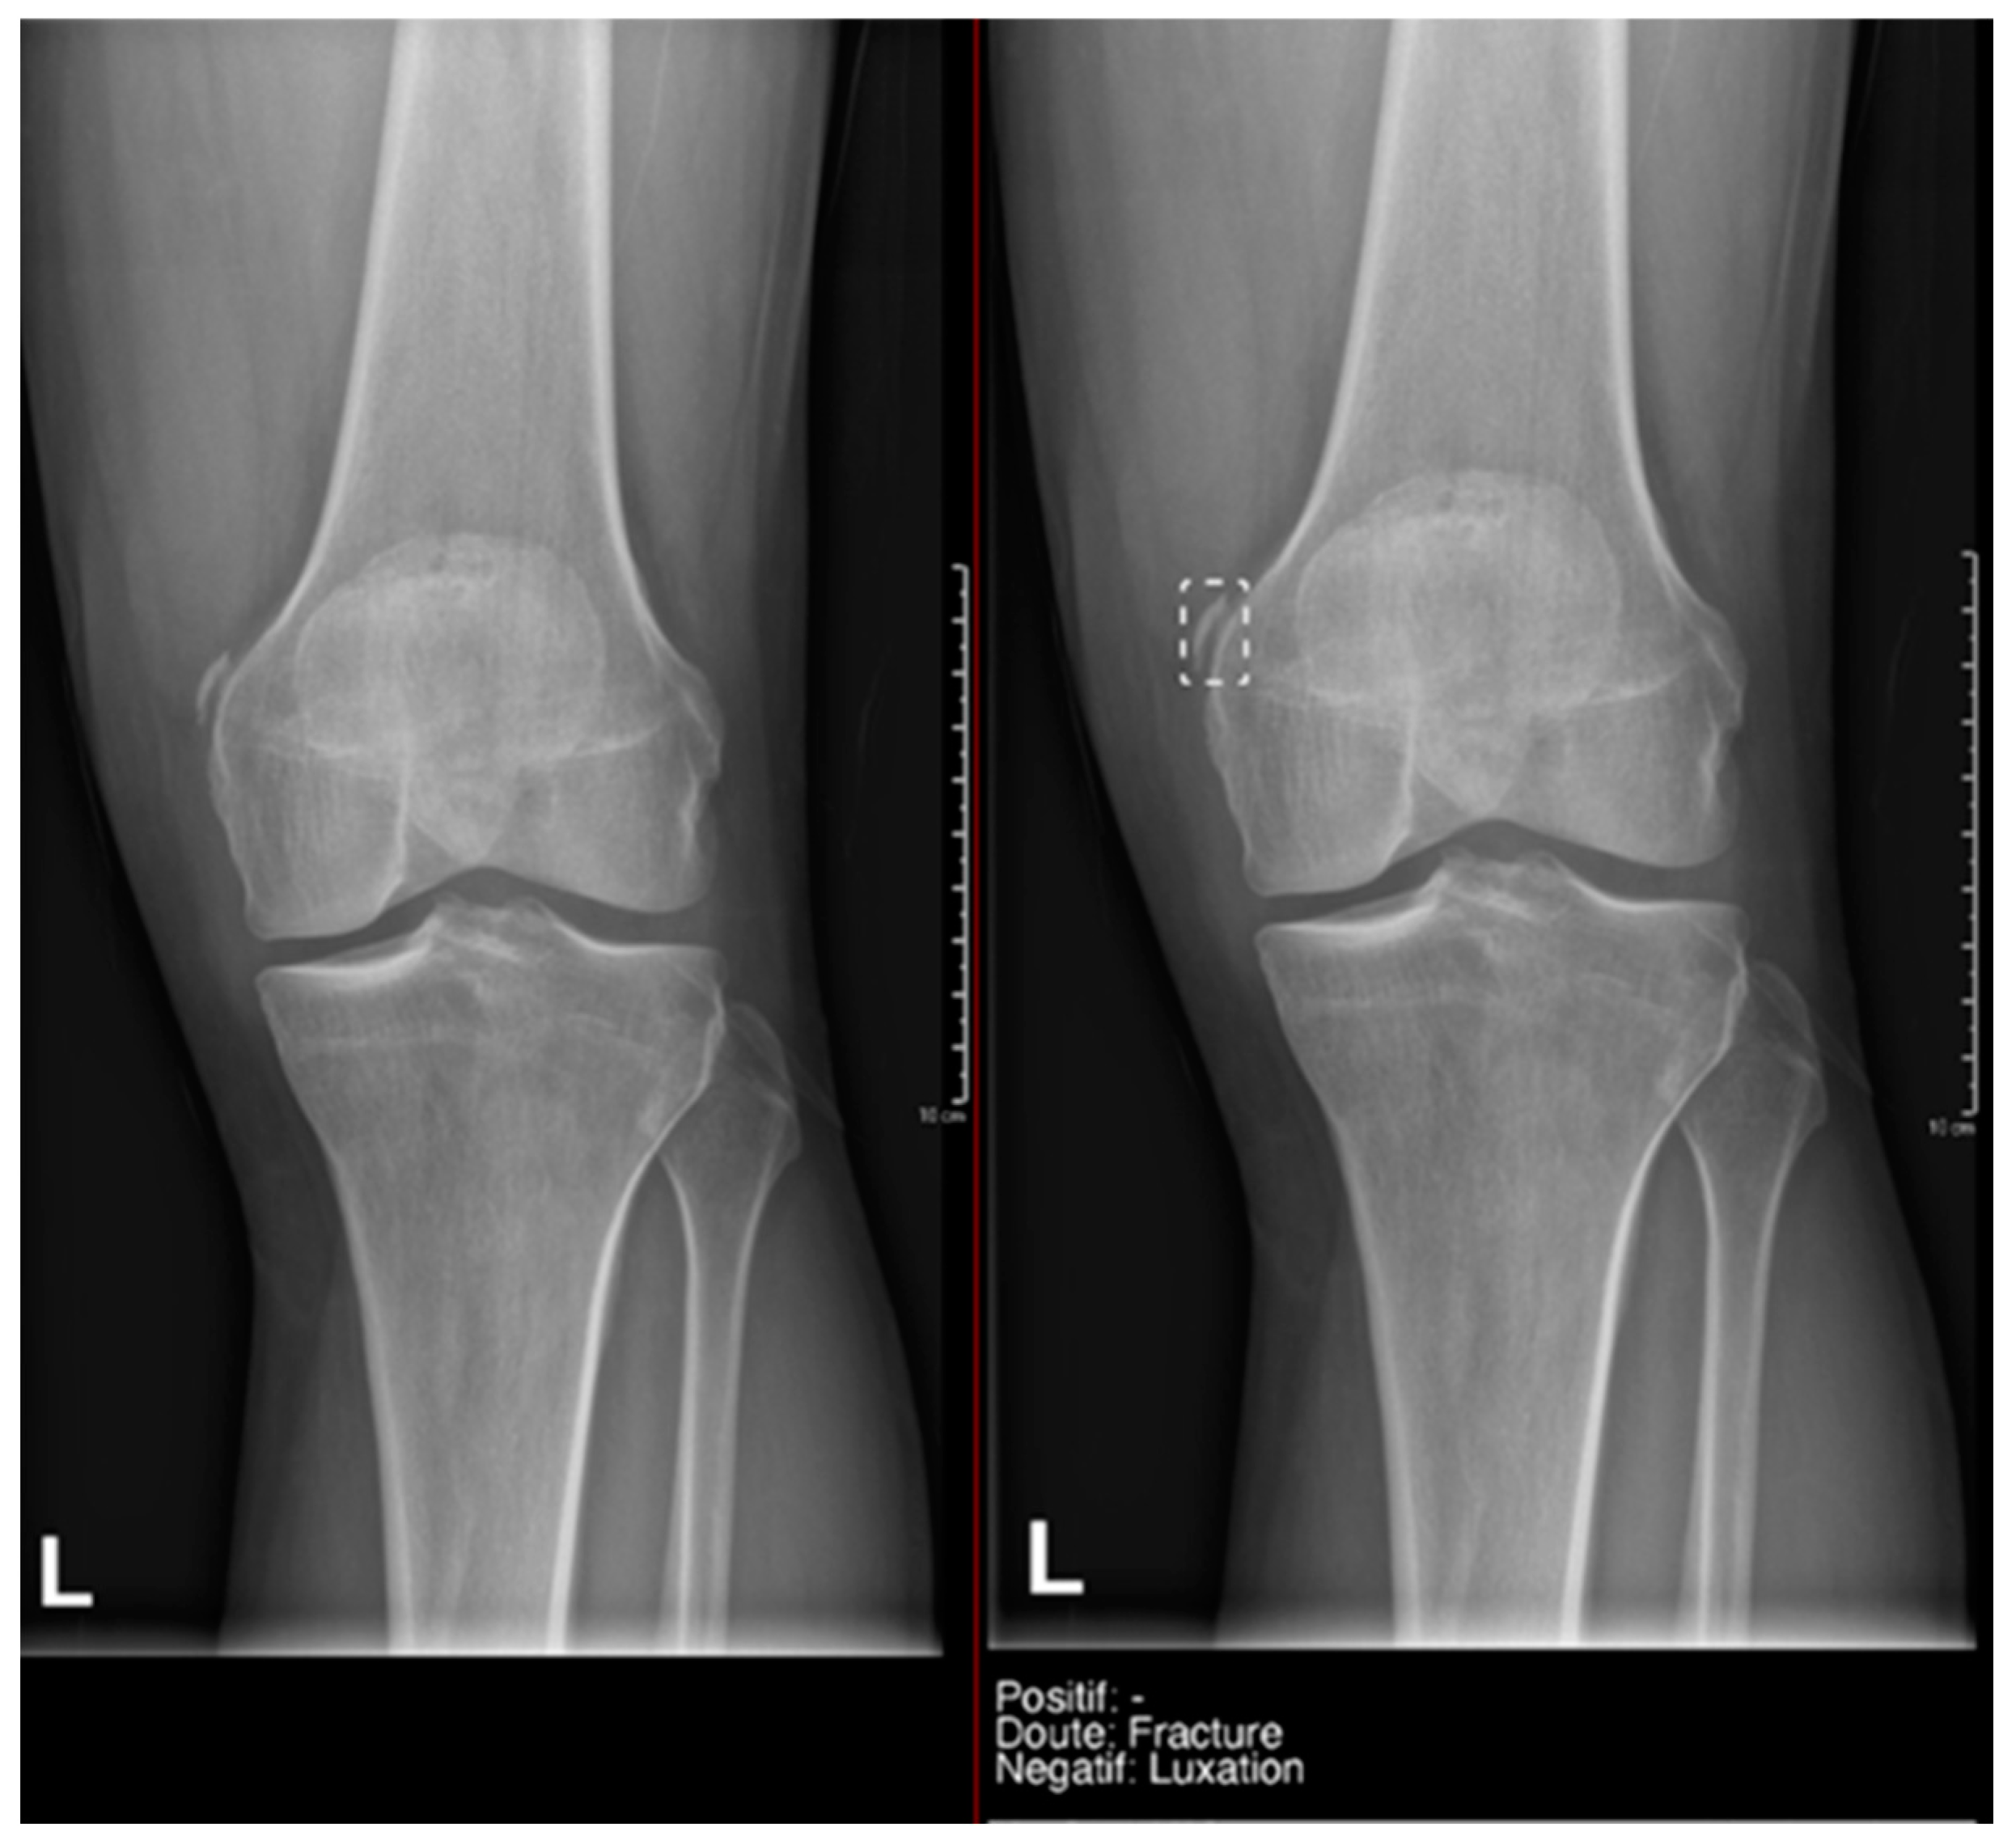

Regarding the detection of dislocations (Table 4), we observed better sensitivity results in the resident’s reading compared to that of the AI, with a high sensitivity of 77.8% in the overall cases, which improved to 84.6% in the large joint group. In contrast, the AI showed lower sensitivity values, with 35% in the overall cases and 35.7% in the large joints. However, specificity values were excellent for all readings and groups, reaching between 99.5% and 100%. (Figure 9 and Figure 10).

Pelvic fracture and coxofemoral dislocation, which was recorded as negative by AI but correctly detected by the radiology resident.

All these results were heavily influenced by the low prevalence of dislocations in our sample. If we refer to the literature, in the study by Regnard et al., they obtained sensitivity and specificity values for AI readings that were higher than those shown in our study, with 89.9 and 99.1, respectively [14]. However, they also align with our research in that the sensitivity and specificity values are higher in the radiologist’s reading compared to AI.